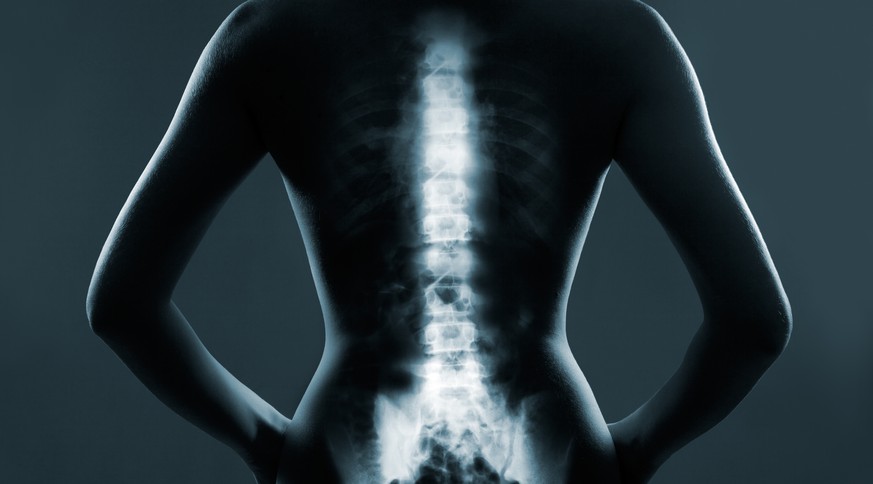

Die Wirbelsäule besteht aus 7 Hals-, 12 Brust-, 5 Lendenwirbeln sowie dem Kreuzbein und dem Steissbein. Die Wirbel sind durch Gelenke miteinander verbunden, so ist sie beweglich. Der Kanal im Inneren der Wirbelsäule ist gefüllt mit Flüssigkeit und beinhaltet die Nerven, welche Organe, Muskel oder andere Körperteile versorgen.

Durch Zwischenwirbellöcher der Wirbelsäule treten diese Nerven aus. Auftretende Verlagerungen oder Verdrehungen der Wirbel verengen diese Zwischenwirbellöcher, verlagern oder verformen die Bandscheibe. Aufgrund des dadurch entstehenden Drucks wird der austretende Nerv gereizt und der zu versorgende Organismus in seiner Funktion beeinträchtigt.

Es können somit z.B. Kopfschmerzen auftreten, Migräne, Schwindel, Konzentrationsstörungen, chronische Müdigkeit, Herzrhythmusstörungen, Magenbeschwerden, Sodbrennen, Menstruationsbeschwerden, Knie-, Hüfte-, Becken-, Schulter- und Kieferbeschwerden.